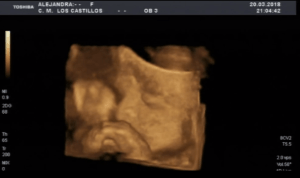

Llaman al teléfono SOS de +Futuro. Son las 11 de la noche, son un grupo de misioneras de extremadura. Acogen y educan a chicas desahuciadas y en riesgo de exclusión social. Una de sus chicas, ya mayor de edad que se ha ido a vivir con la madre de su novio esta de 26 semanas de embarazo. Quieren que aborte todo su entorno. Ella no. Un médico y el abortorio «Los Arcos» de Badajoz dicen que su niño viene con hidrocefalia. Afirman con contundencia que la madre corre peligro de morirse. (fotos de una ecografía de Alexia, la hija de dos voluntarios de la asociación de 26 semanas).